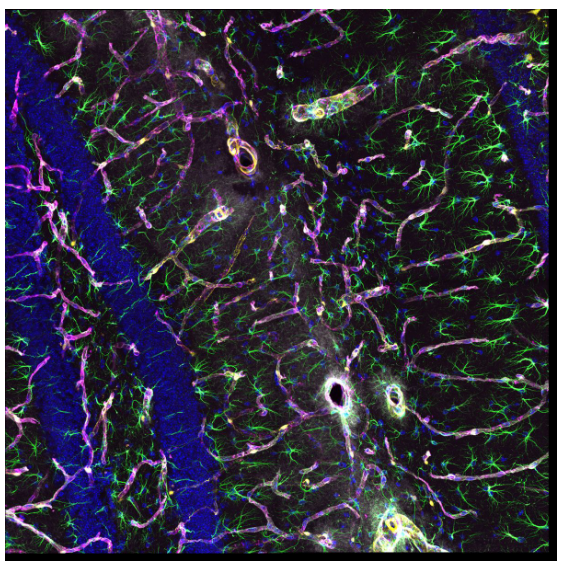

小鼠海马体的神经血管单位。蓝;DAPI细胞核,绿色;GFAP AF488型。星形胶质细胞,黄色;DsRed周细胞,品红色;血管胶原IV AF647基底膜,灰色;AQ-4型。星形胶质细胞水通道。

样品来源:Hiroshi Hama 和 Atsushi Miyawaki,RIKEN CBS 细胞功能动力学。